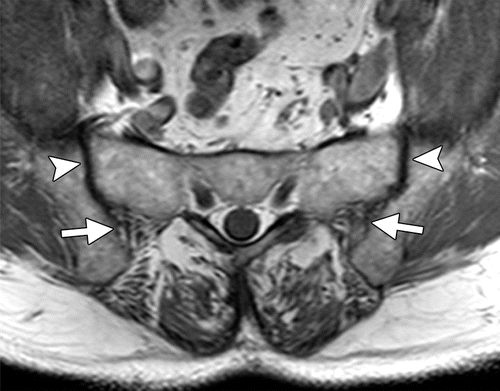

An MRI scan of the sacroiliac joints displays the sacroiliac joints, which are the joints that connect the central sacrum bone to the ilium bones of the pelvis on each side. An MRI of the sacroiliac joint can detect early stages of joint inflammation that may not be detectable on an x-ray.